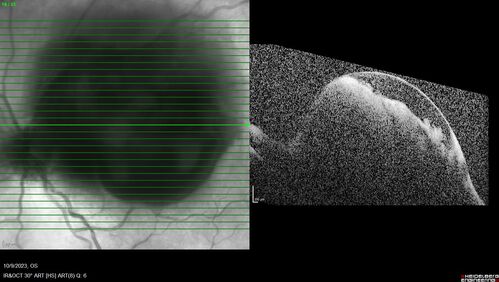

Ruptured Retinal Arterial Macroaneurysm - Submacular hemorrhage and BRAO

81 year old female with vision loss for a few days. Coumadin was high with INR at 3.1 VA 6/200